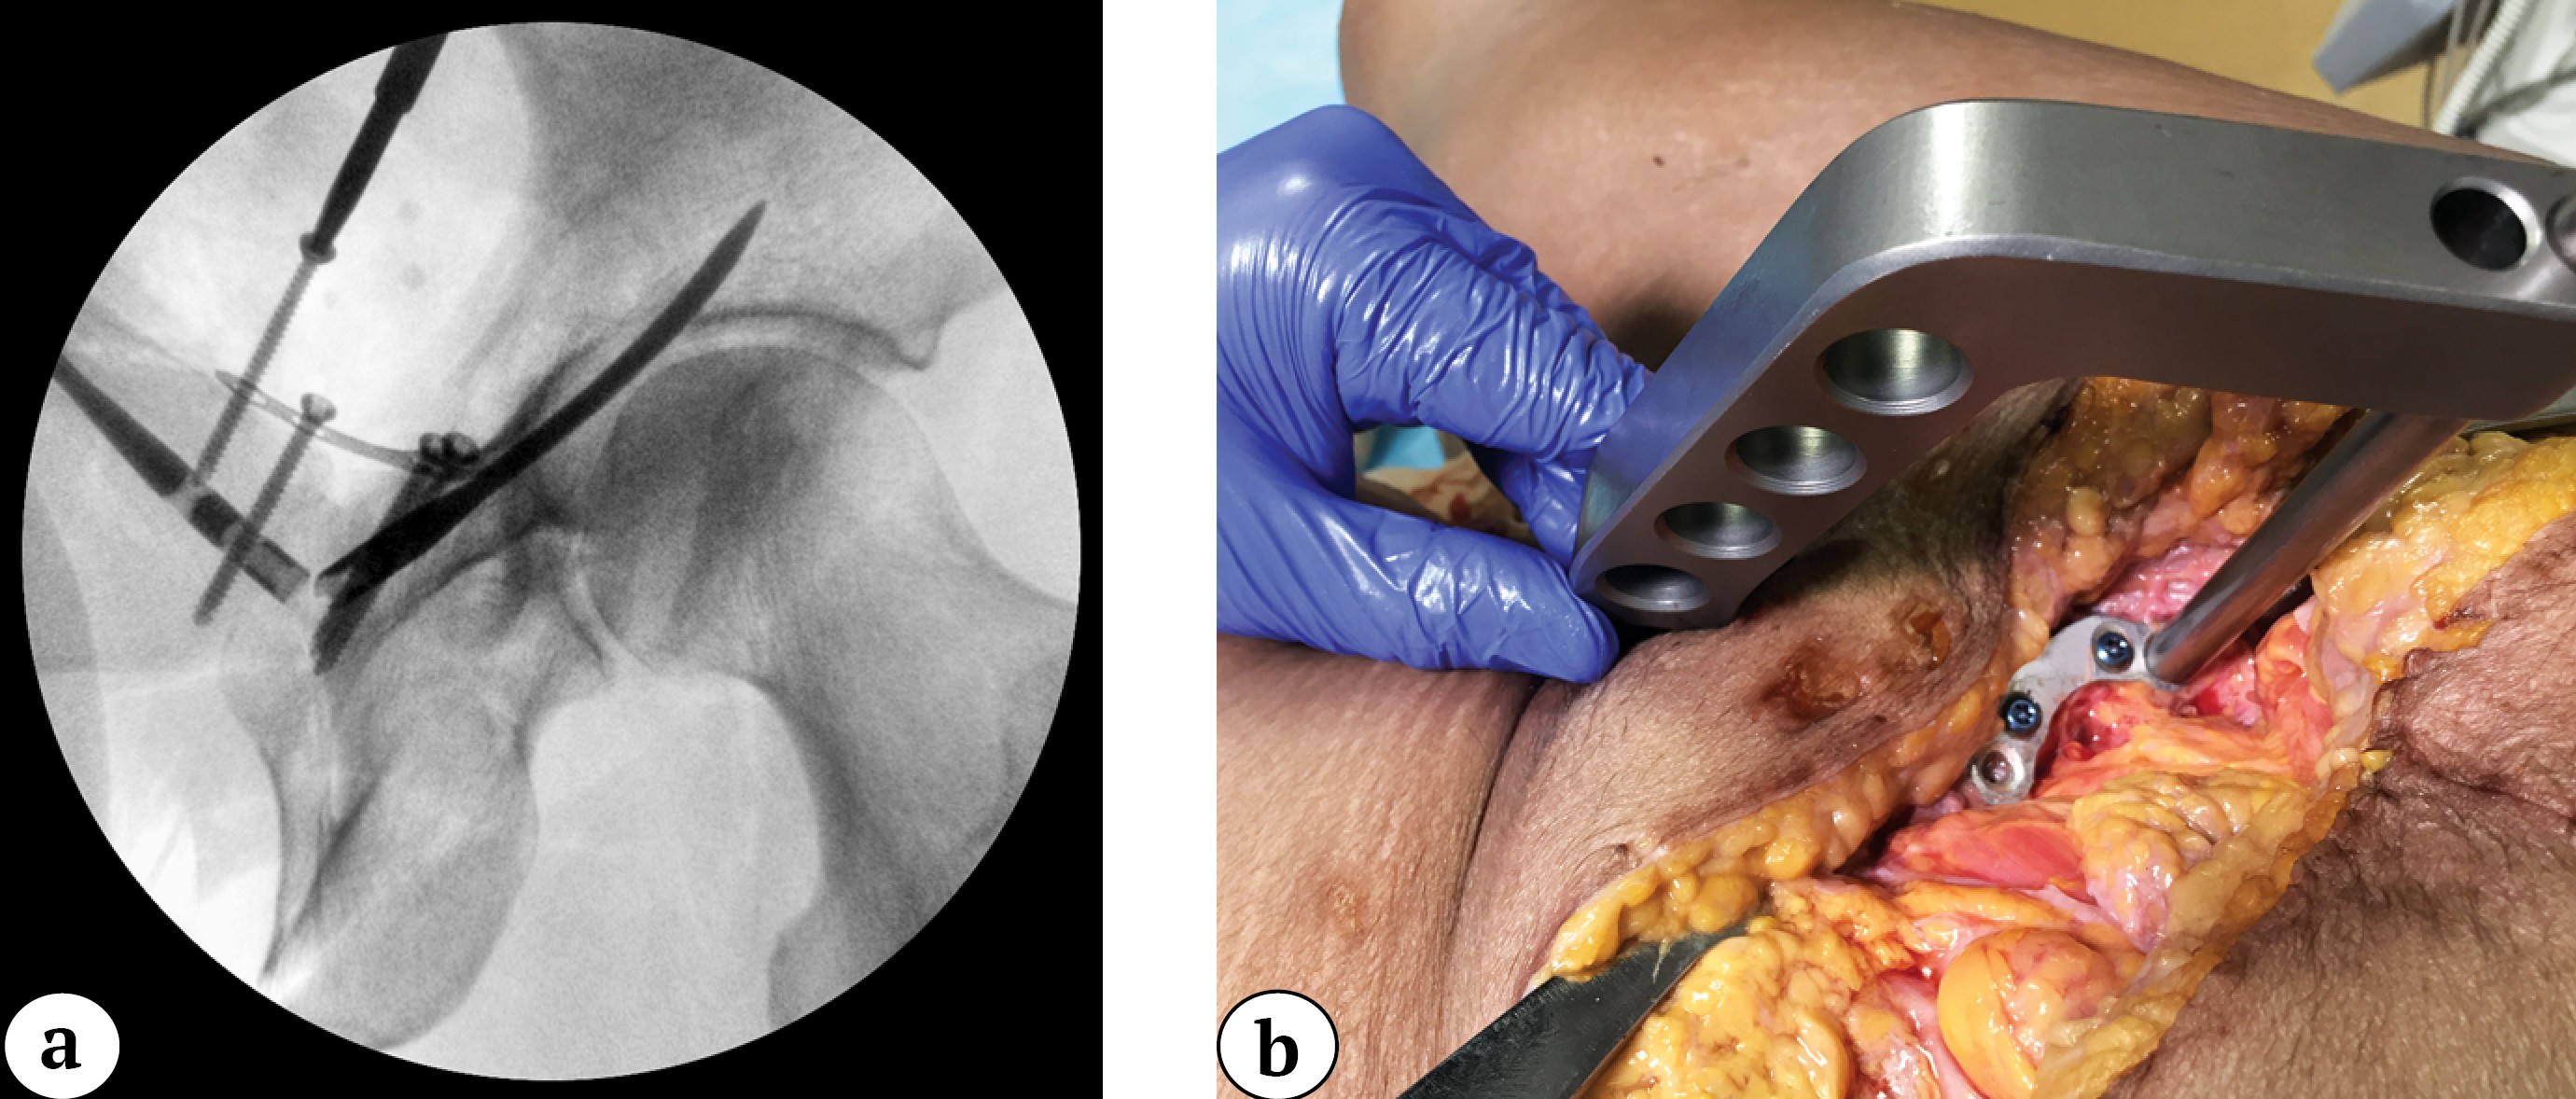

Sequential fixation of the pubic rami fractures was then performed using locking nails on both sides through a 1-cm contralateral skin puncture located below the Pfannenstiel incision, but without inserting the locking screws. Without removing the guide from the last inserted nail, the plate was positioned so that the midpoint of the implant lay exactly over the reduced pubic symphysis (Figure 3).

Figure 3. Intraoperative inlet view of the pelvic with nails inserted into both pubic bones (a); the plate is positioned at the midpoint of the superior symphyseal border via the surgical approach (b)